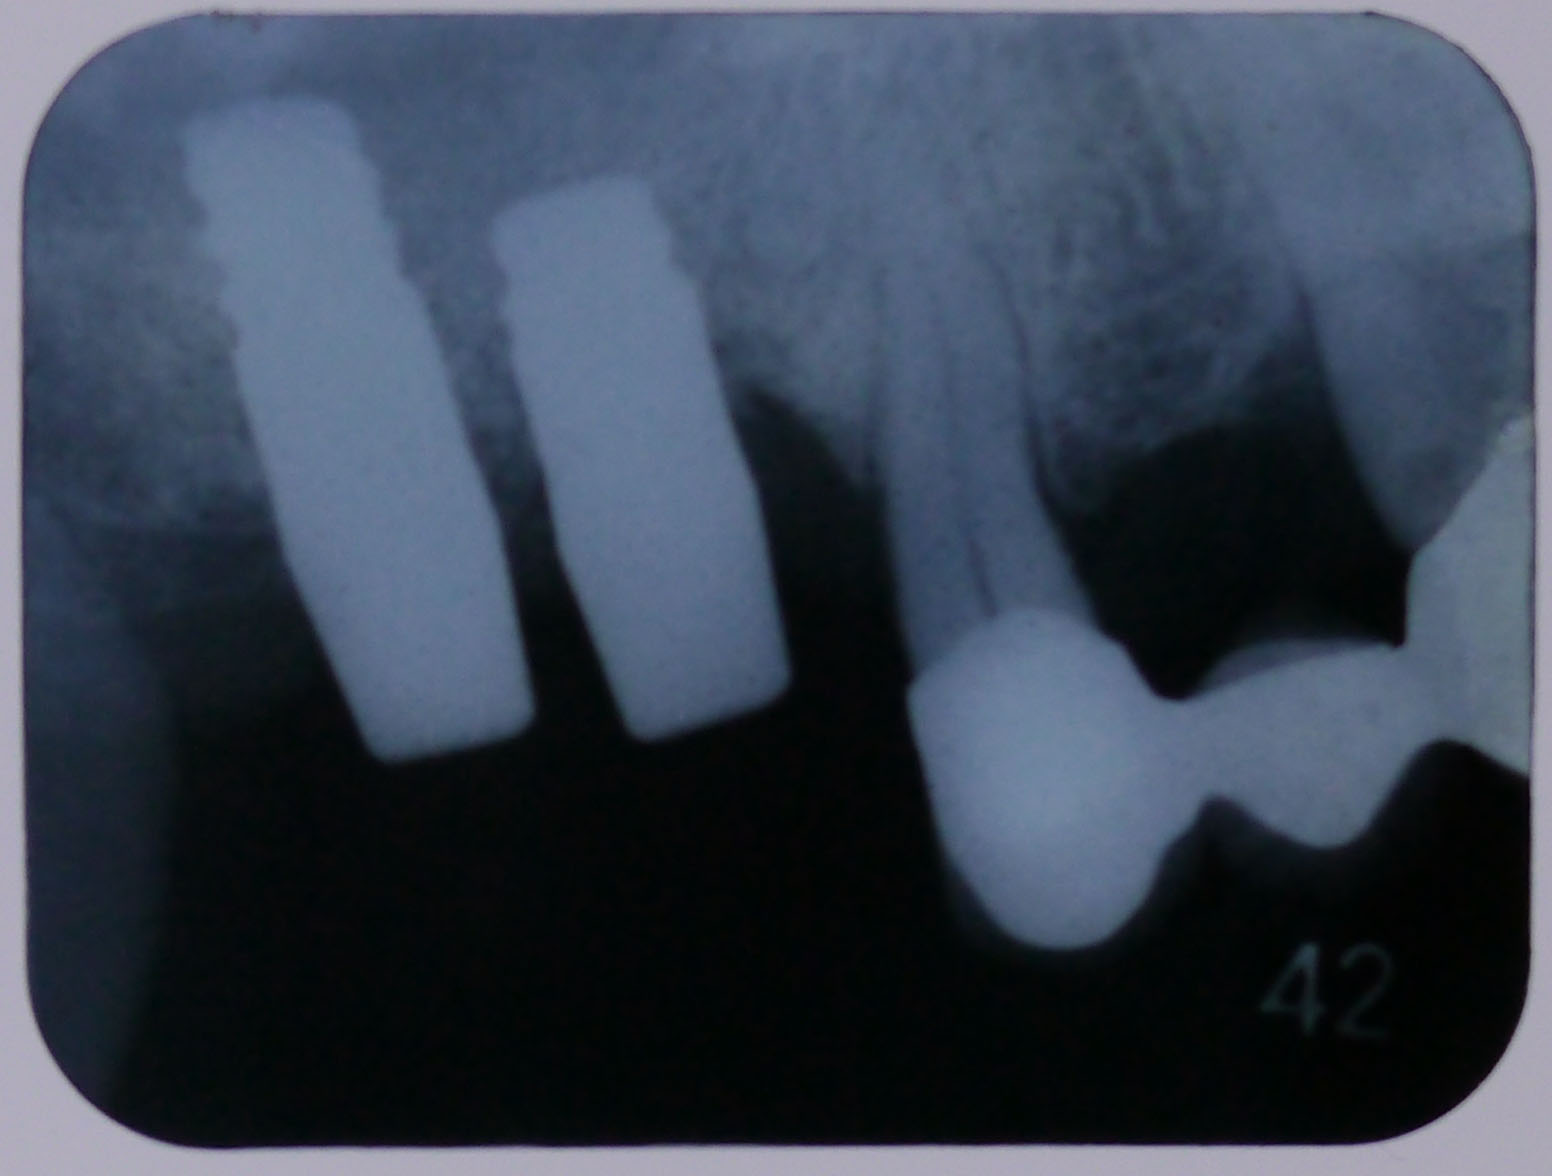

【平成26年3月26日CT画像】

CT画像4

右上7番、インプラントの先端近くまで骨が出来ている

CT画像5

右上6番、インプラントの先端まで骨が出来ている

【レントゲン画像3】

平成29年3月3日定期検診時

十分に骨が維持されている